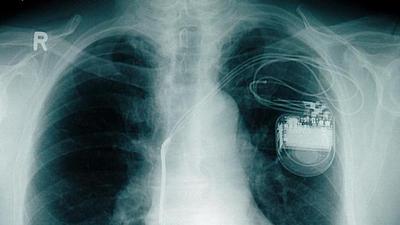

Dispositivo obtém energia a partir dos próprios batimentos cardíacos. Caso funcione em seres humanos, invenção pode representar um grande alívio para pacientes com o implante.